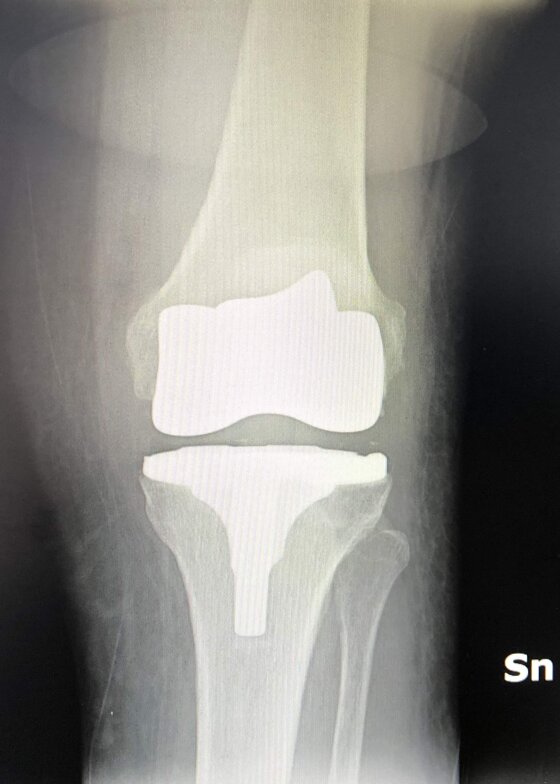

Radiografie post-operatorie in AP e LL di intervento chirurgico di artroprotesi cementata di ginocchio in pz donna con sovrappeso. In questo caso è stata utilizzata una protesi postero-stabilizzata (PS) con sacrificio quindi del legamento crociato posteriore (LCP)

Radiografie post-operatorie in AP e LL di intervento chirurgico di artroprotesi cementata di ginocchio. In questo caso è stata utilizzata una protesi a conservazione del LCP (CR) della stessa marca della protesi precedente

Radiografie post-operatorie in AP di interventi chirurgici di artroprotesi cementate di ginocchio eseguiti in due pz con allergia ai metalli (nichel). Sono state utilizzate due protesi di due arche differenti, entrambe anallergiche (nichel-free) con conservazione del LCP (CR)